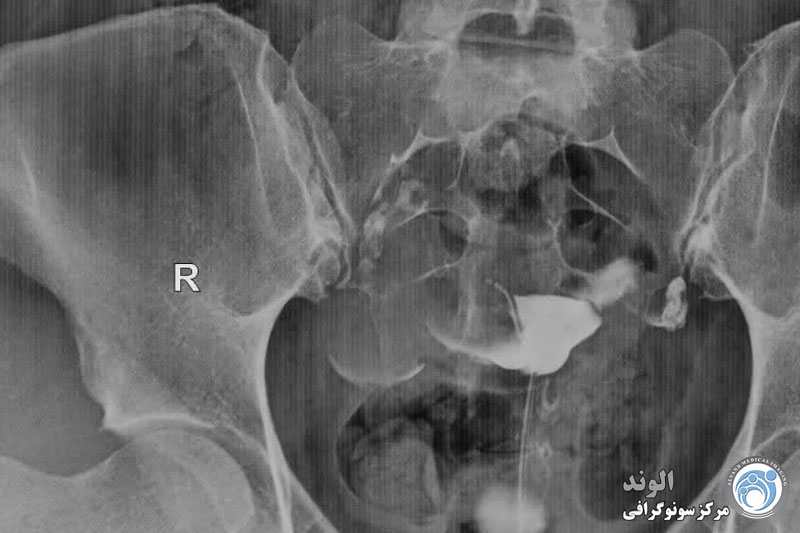

بیمار در وضعیت زنان (به پشت خوابیده، زانوهای خم شده و از هم باز)، زیر دستگاه اشعه ایکس قرار می گیرد. پزشک یک اسپکولوم را وارد واژن میکند، سپس یک کانولا را در دهانه رحم قرار میدهد که از طریق آن یک ماده حاجب تزریق میکند. این به داخل رحم و لوله های فالوپ گسترش می یابد. اشعه ایکس برای مشاهده پیشرفت خوب محصول و تجسم اندام ها گرفته می شود.

هیستروسالپنگوگرافی توسط رادیولوژیست انجام می شود. معاینه بدون بیهوشی انجام می شود. بیمار در موقعیت "زنان و زایمان" مستقر می شود. پزشک اسپکولوم را قرار می دهد، دهانه رحم را ضد عفونی می کند و سپس یک پروب را با روش طبیعی وارد رحم می کند. او به تدریج ماده حاجب را تزریق می کند. به طور معمول، ماده حاجب به تدریج رحم و لوله های فالوپ را کدر می کند تا زمانی که به حفره صفاقی منتقل شود.

چندین عکس رنگی رحم قبل، حین و بعد از تزریق محصول گرفته می شود و این در موقعیت های مختلف:

اشعه ایکس بدون آماده سازی (جستجو برای کلسیفیکاسیون لگن)؛

اشعه ایکس پر شدن ضعیف (پولیپ ها یا فیبروم های زیر مخاطی را برجسته می کند).

اشعه ایکس پر شدن لوله (ارزیابی وضعیت مخاط لوله).

عکس پروفایل (ارزیابی موقعیت رحم و مسیر لوله های فالوپ)؛

اشعه ایکس دیررس (بررسی گردش خون صفاقی، جستجو برای چسبندگی لگن).